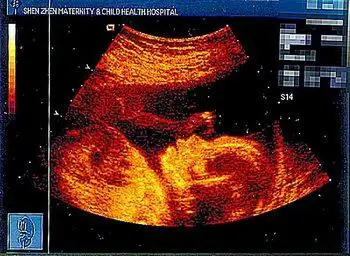

医院卖可辨性别胎儿写真